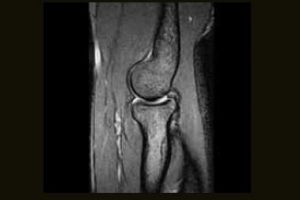

Clinical Images